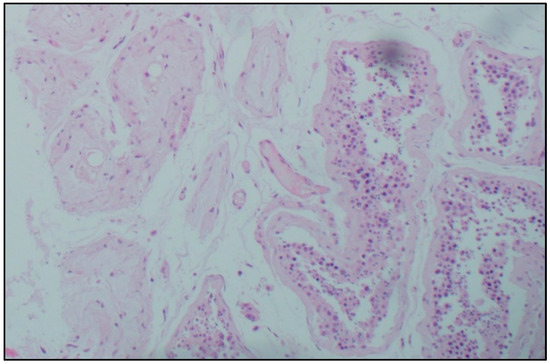

Immunohistochemical study. IHC-assessment of the testicles of Group I compared with the norm revealed a significant increase in the number of immunopositive germ cells, mainly located in the adluminal compartment of the convoluted seminiferous tubules, stained with antibodies to the SARS-CoV-2 spike protein and nucleocapsid, which was more pronounced in the group of elderly and senile age (Table 2, Figure 2). A similar IHC pattern was observed in Leydig cells and endotheliocytes of peritubular blood vessels (Table 2, Figure 2).

Figure 2.

Immunohistochemical pattern of germinal epithelium in patients with confirmed novel coronavirus infection. Stained with hematoxylin, magn. ×200.

In the group of COVID-19-positive patients, a significant increase in the number of IHC-stained ACE2 cells of the late stages of spermatogenesis was revealed compared to the control group, and the largest number of positive cells was detected in the cohort of patients of senile and elderly age (Table 2, Figure 2).